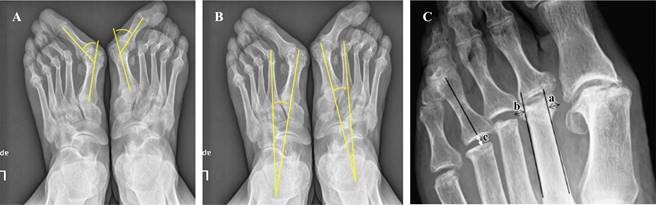

Evaluación radiográfica. Se realizó una evaluación de la luxación de la articulación MTF, el espacio de artroplastía de resección y el tamaño de los osteofitos por remodelación del muñón metatarsal. El espacio de artroplastía de resección se definió como la distancia mínima desde el punto de intersección entre el eje longitudinal y el extremo proximal de la falange proximal hasta el margen distal del muñón correspondiente del metatarsiano. El tamaño de los osteofitos se definió como la suma de la longitud de dos líneas perpendiculares desde el punto más prominente del osteofito hasta una línea tangencial a lo largo de la cortical medial y lateral del metatarsiano. La luxación de la articulación MTP y potenciales recurrencias se evaluaron antes de la cirugía, en el postoperatorio inmediato y en la última visita de seguimiento. El espacio de artroplastía de resección se evaluó en el postoperatorio inmediato y en la última visita de seguimiento. El ángulo intermetatarsiano (IMA) y el ángulo de hallux valgus (AHV) se evaluaron antes de la cirugía y después de la cirugía en la última visita de seguimiento. El tamaño de los osteofitos se midió en la última visita de seguimiento. Todas las medidas se basaron en radiografías anteroposteriores y laterales estándar de los pies en carga (Figura 1).

Tomada de: Matsumoto T, et al.16

Figura 1: Ilustración de las medidas radiográficas. A) Ángulo de hallux valgus. B) Ángulo intermetatarsal. C) Espacio de artroplastía de resección ( c ) y formación de osteofitos por remodelación en el muñón metatarsal (a + b ).